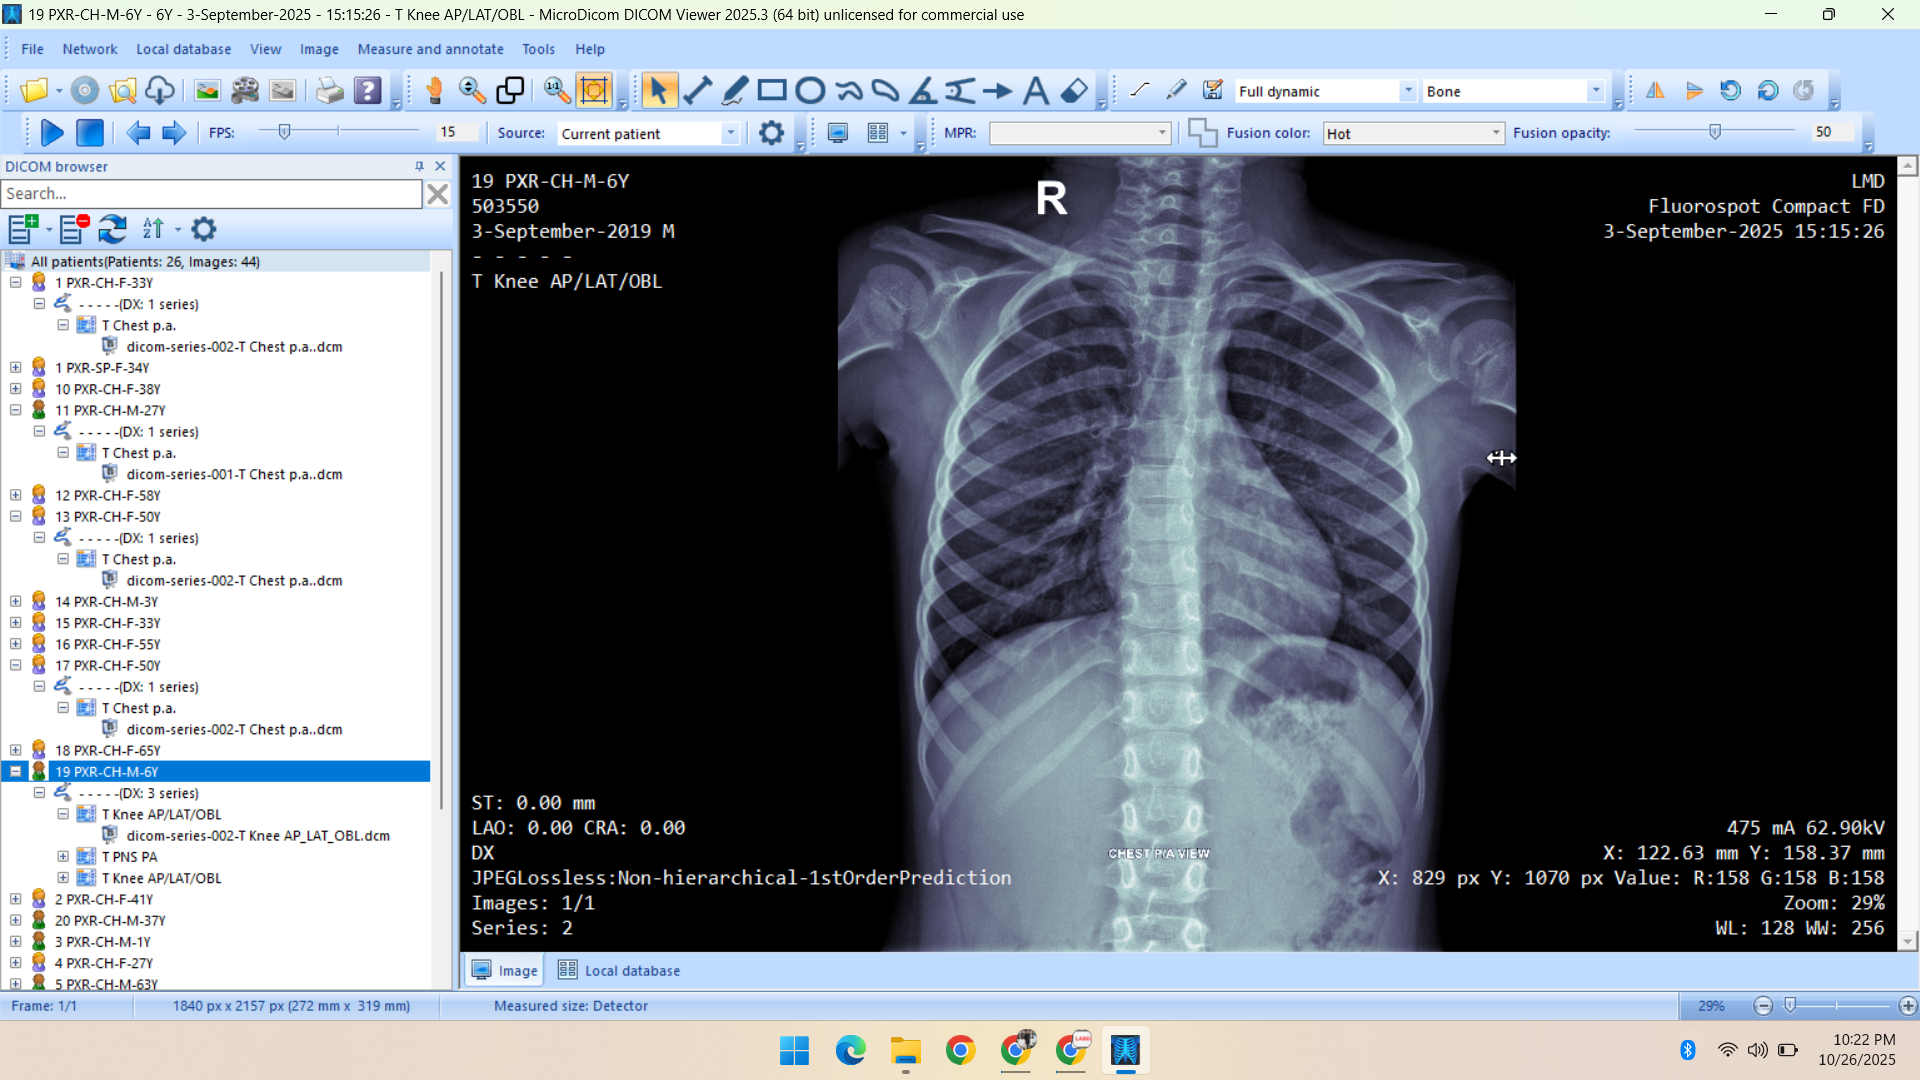

- Radiology Data – CT Scans, X-Rays, MRI, Echocardiography, Ultrasound.

Healthcare & Medical Data Supply

We specialize in healthcare datasets including radiology (CT, X-ray, MRI, Ultrasound, Echocardiography), pathology microscopy, and histopathology images — all ethically sourced and research-ready.

- X-Ray